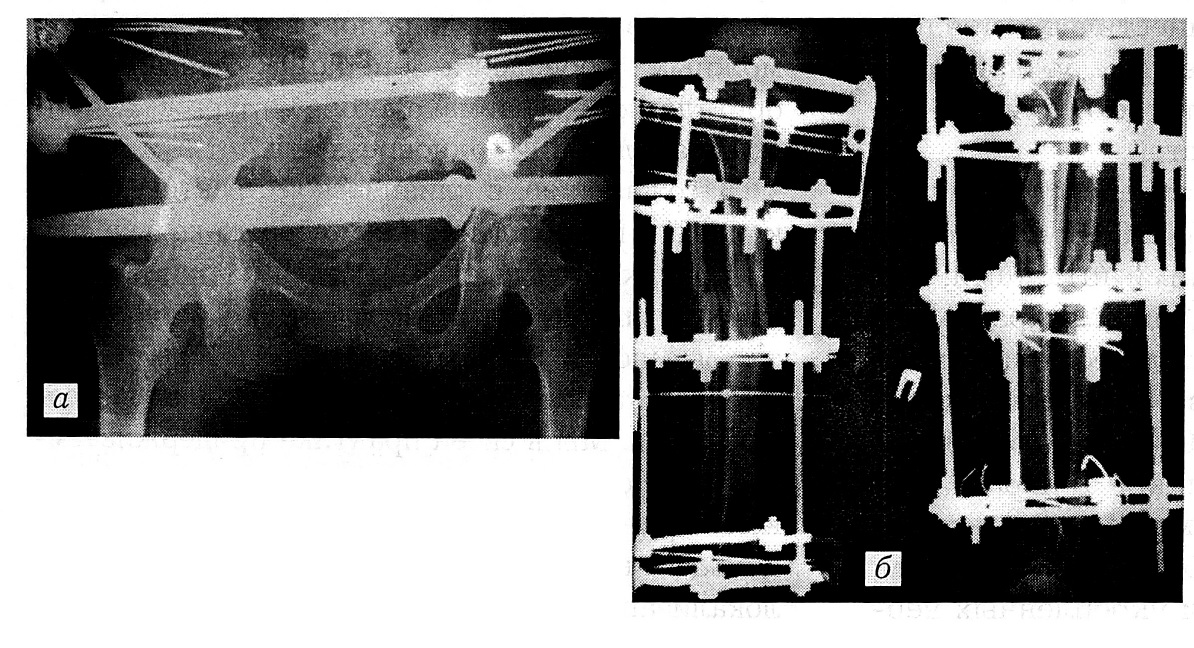

Рис. 2. Рентгенограммы той же больной после операции в день поступления. а — стабилизация тазового кольца спицевым аппаратом наружной фиксации: закрытая репозиция, конфигурация тазового кольца восстановлена; б — наружный чрескостный остеосинтез перелома голени аппаратом Илизарова.

После окончания операции на брюшной полости двумя бригадами одновременно произведены закрытая репозиция и стабилизация тазового кольца аппаратом наружной фиксации и чрескостный остеосинтез перелома правой голени аппаратом Илизарова (рис. 2).